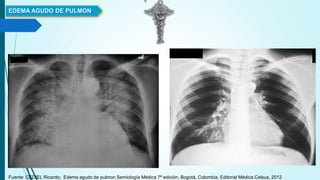

 Radiografía de tórax con

edema agudo de Pulmón

 Radiografía de tórax

Fuente: CEDIEL Ricardo; Edema agudo de pulmon Semiología Médica 7ª edición, Bogotá, Colombia, Editorial

Médica Celsus, 2012

 Aumento de la silueta Cardiaca.

 Congestión y edema Pulmonar parahiliar bilateral que

(Alas de Mariposa)